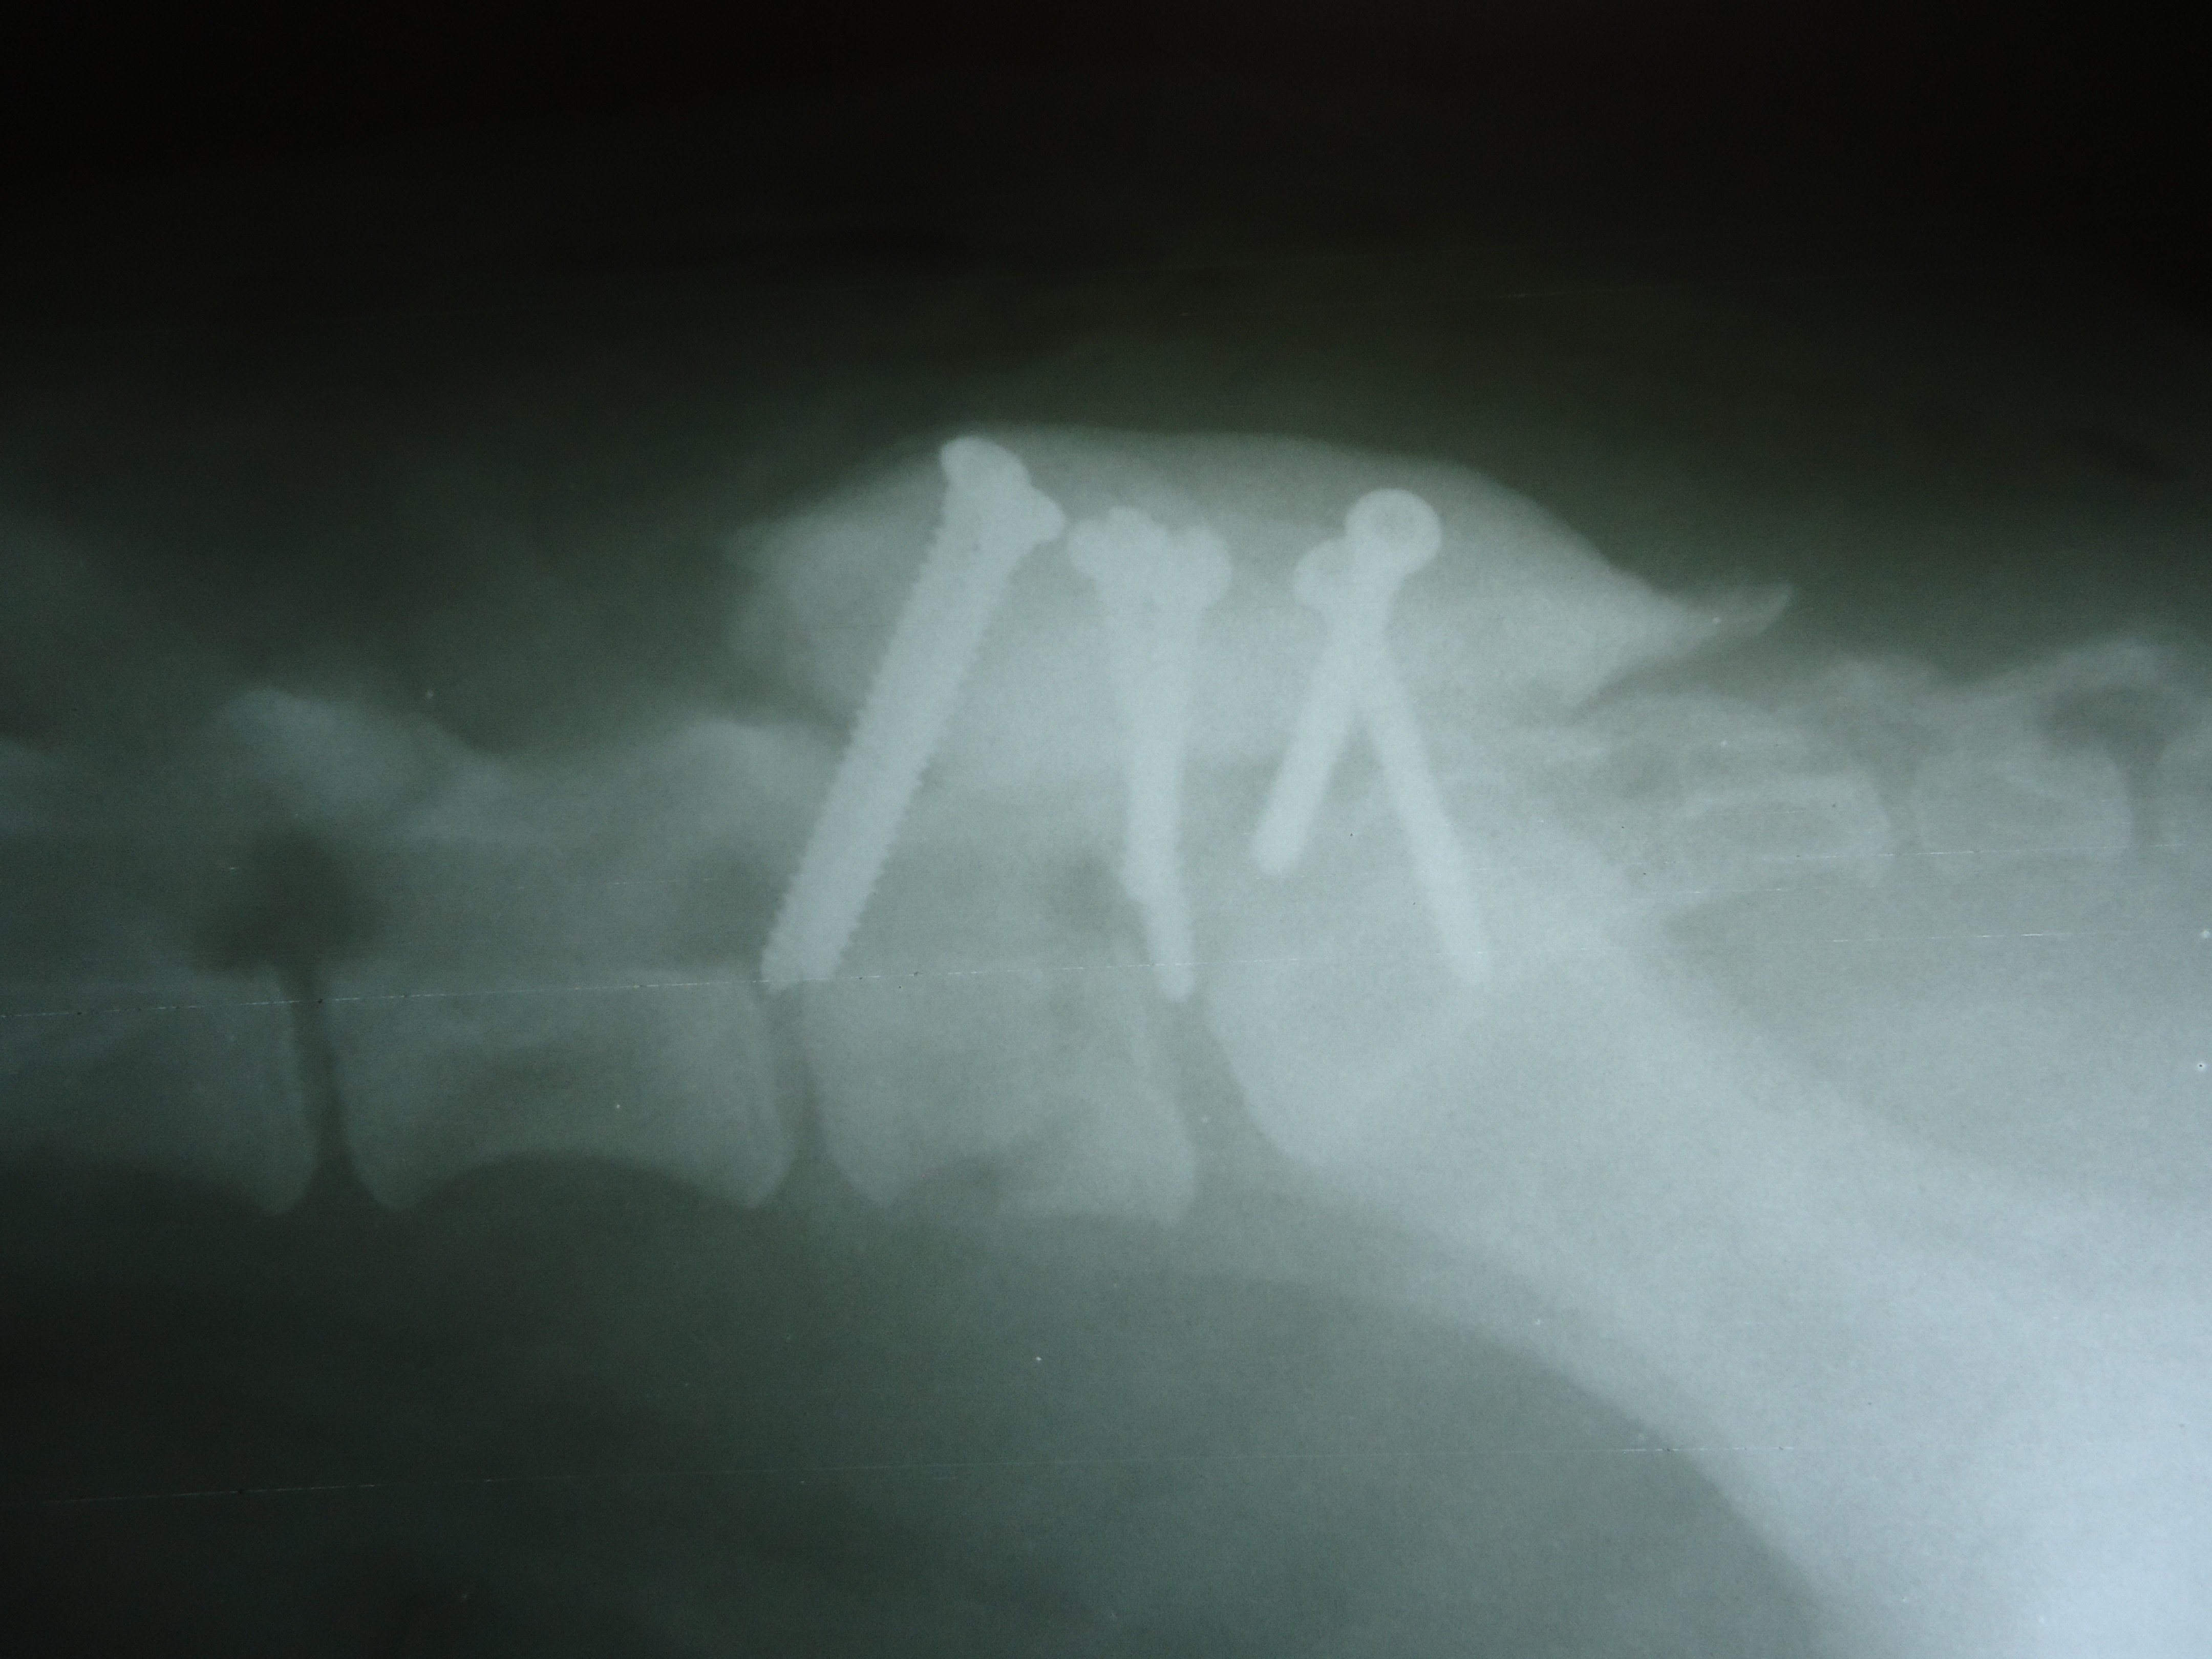

Заболевания позвоночника у домашних животных: диагностика и лечение

Раздел: Визуальные истории